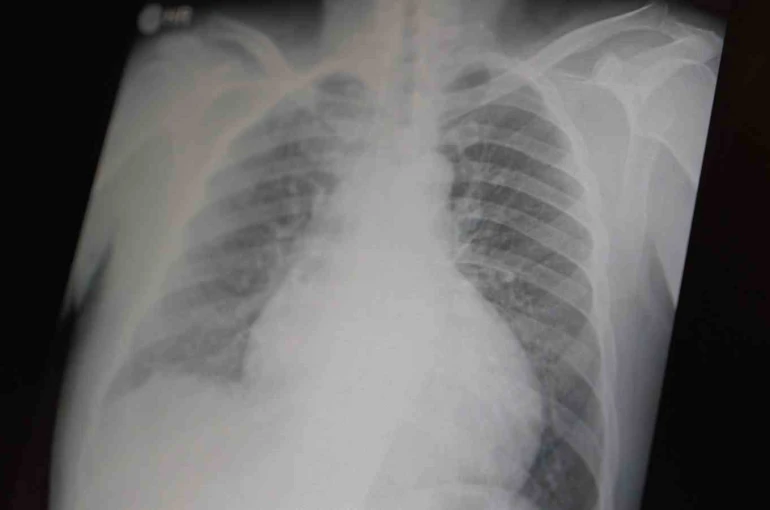

Prof. Dr. Şevket Özkaya, çocukları ve gençleri etkileyen bağımlılıklar hakkında açıklamalarda bulundu. Metamfetaminin sentetik bir uyuşturucu olduğunu ve kullanımının ölümcül sonuçlar doğurduğunu ifade eden Özkaya, "Tüm dünyada çocukları ve gençleri etkileyen iki önemli bağımlılıktan bahsetmek istiyorum. Bunlar metamfetamin ve kokain bağımlılığıdır. Metamfetamin en ölümcül, en çok bağımlılık yapan, okul çağında en kolay ulaşılabilen bir sentetik uyuşturucudur. Kullanıma bağlı ciddi akciğer ve karaciğer sorunları ortaya çıkıyor. Çok küçük dozlarda bile anında bağımlılık yapabiliyor ve tedaviyle bırakılması çok zor bir bağımlılıktır" dedi.

Açıklamalarında, her iki uyuşturucunun beyin hasarı oluşturduğunu ve nöro sinir hücrelerini harap ederek solunum ve kalbin durmasına sebep olduğunu vurgulayan Özkaya, "Metamfetamin tüm dünyada bir sorun olmanın ötesinde, ülkemizde de gençlerimizi etkileyen toplumsal bir sorun olarak görülmelidir" ifadelerini kullandı.